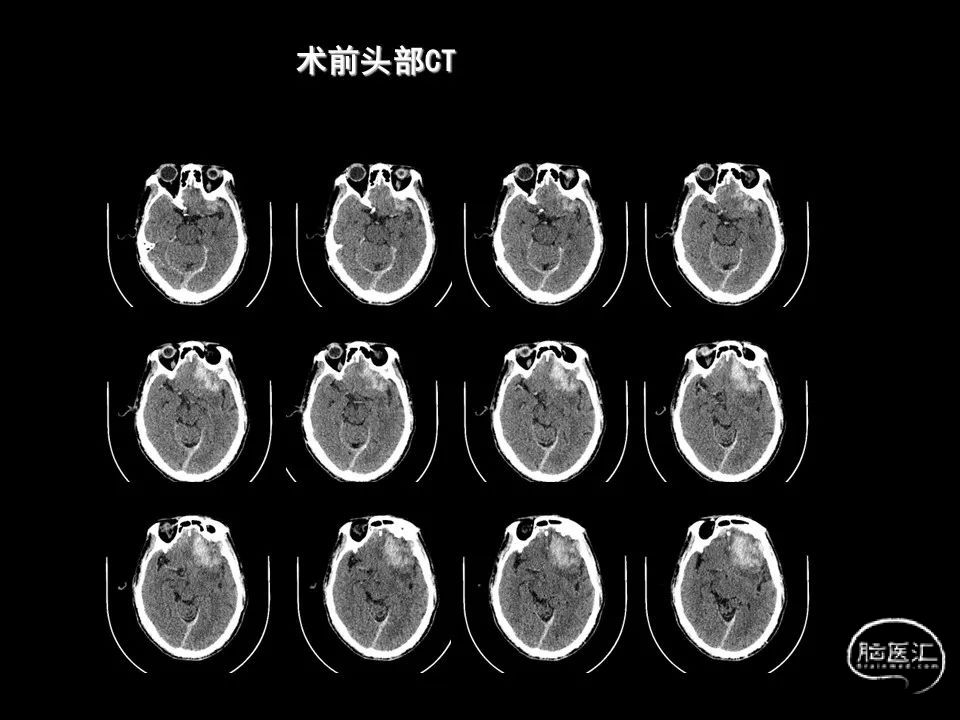

今天为大家分享的是《监测有道丨颅脑创伤-神经重症周刊》第338期,由海南省人民医院朱蔚林教授带来的:2例脑出血微创手术,欢迎阅读、分享。

主要从事神经内镜下垂体腺瘤、高血压脑出血手术,鞍区肿瘤,颅底肿瘤,脑膜瘤、听神经瘤、胶质瘤等显微外科手术,颅脑创伤,脑积水、蛛网膜囊肿、颅内感染等救治